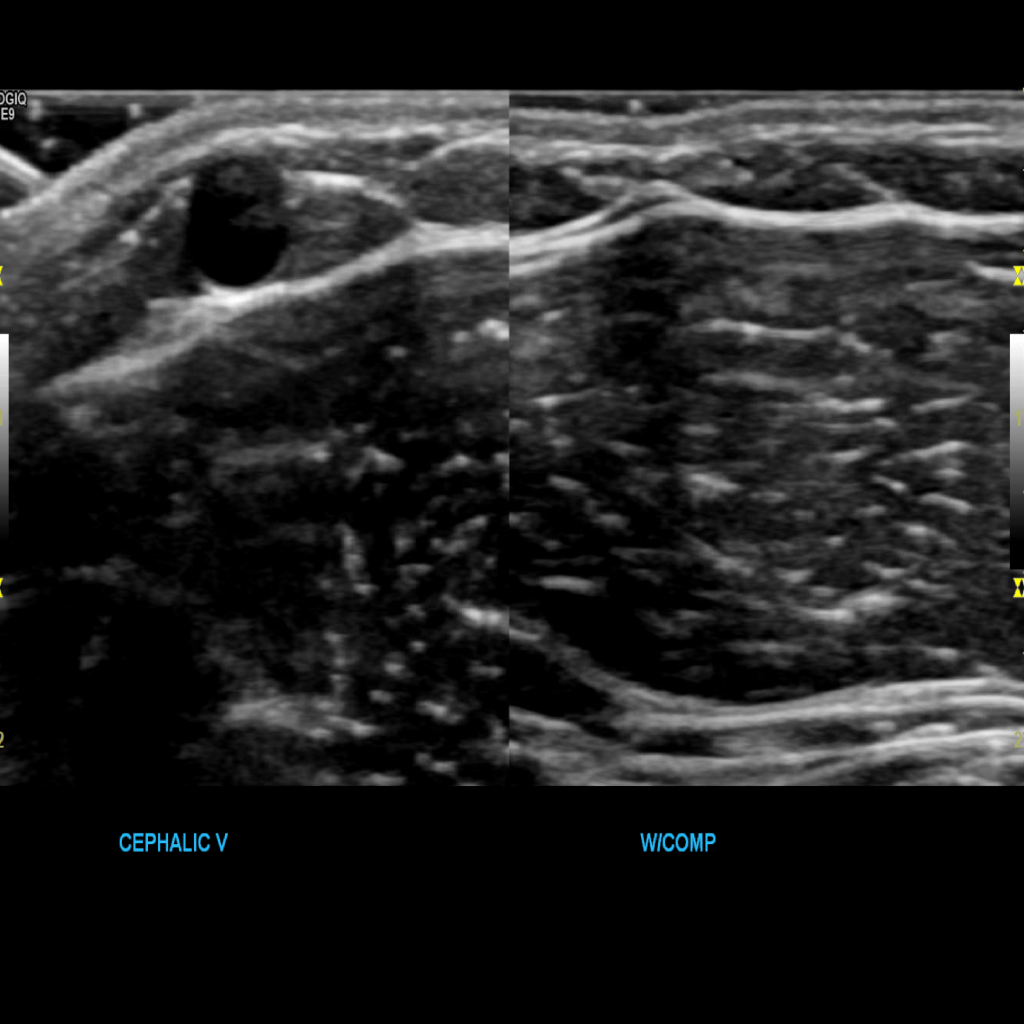

Scan the cephalic vein in grey scale, compression, color doppler and spectral doppler

Thrombus of the right basilic vein